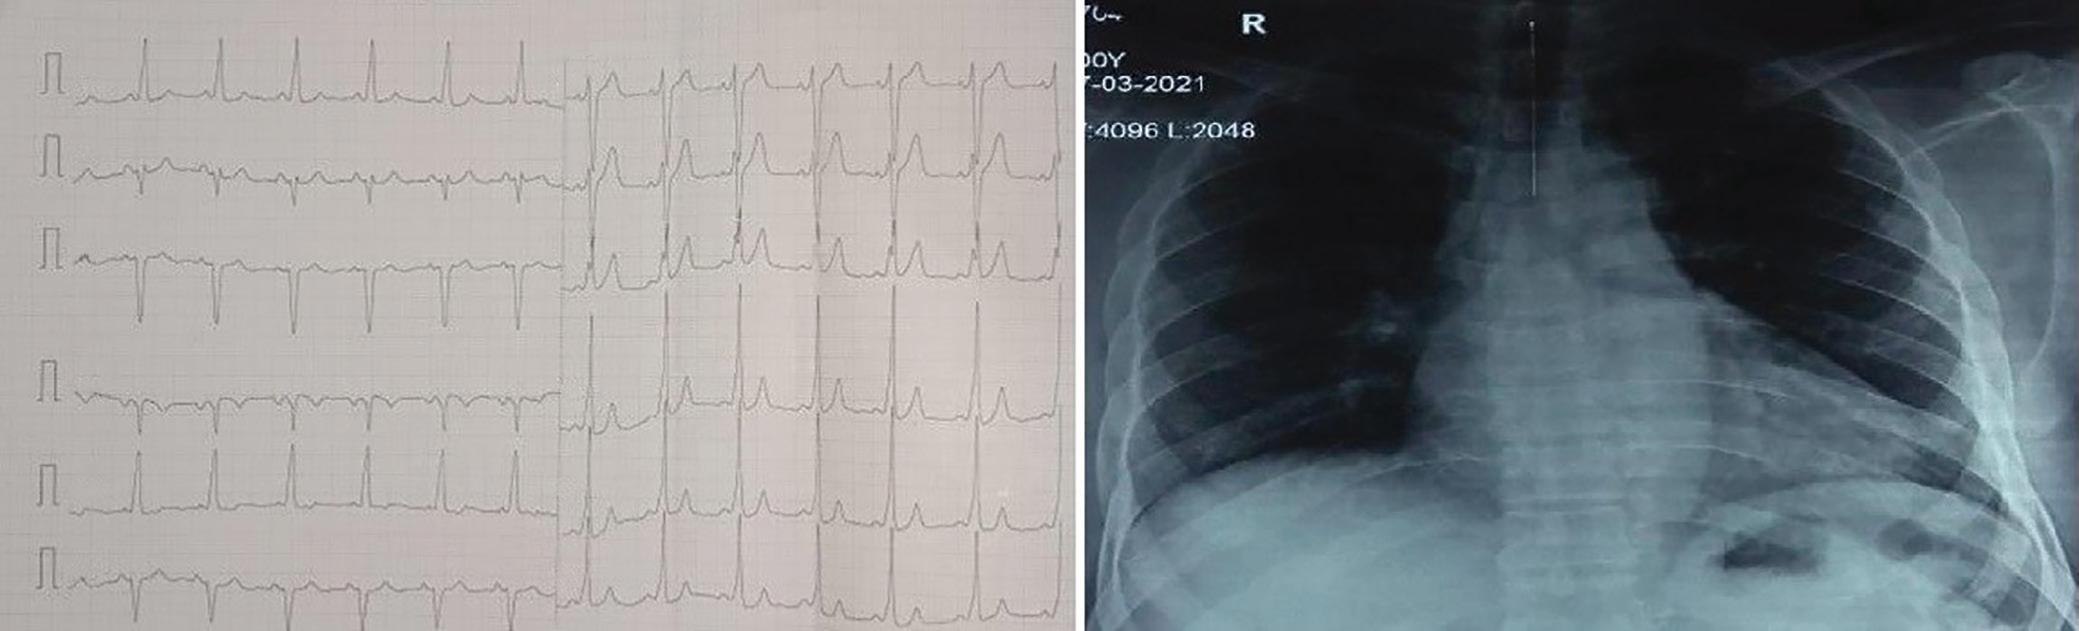

A 57-year-old man presented with a three-decade history of recurrent episodes of palpitation with alarming jugular venous pulsation, but without syncope. Each episode spontaneously reverted to the normal sinus rhythm 6–8 hours after the onset. Cardiac auscultation raised the suspicion of underlying rheumatic mitral stenosis. A 12-lead ECG was suggestive of a WPW pattern with a right posterior septal accessory pathway (Figure 1A). A chest X-ray in the posterior–anterior view was consistent with cardiac auscultation (Figure 1B). A transoesophageal echocardiogram confirmed rheumatic mitral stenosis (Figure 2A and Supplementary Material Video 1). The pliable mitral valve area was 0.8 cm2 and the mean gradient was 17 mmHg at a heart rate of 87 BPM. The coronary angiogram was normal.

The day before the procedure, the patient developed an episode of palpitation during the clinical round. A 12-lead ECG revealed atrial flutter with right bundle branch aberrancy on metoprolol succinate (Figure 2B). The patient’s blood pressure was 124/80 mmHg. Oral verapamil was initiated and the atrial flutter reverted to normal sinus rhythm.

Figure 1: ECG and Chest X-Ray

Report confirmed by I II IR aVR V1 V2 V3 V4 V5 V5 aVL aVP A B A: A 12-lead ECG showing the Wolff–Parkinson–White pattern with a possible right posterior septal accessory pathway because the R/S ratio is <0.5 in V1 and V2 and <1 in the inferior leads. B: Chest X-ray in the posterior–anterior view showing mitralisation of the left heart border, double atrial shadow on the right

side and a horizontal left bronchus. A: There was significant mitral stenosis and the mean mitral valve gradient of 16 mmHg prior to the balloon mitral valvotomy. B: Atrial flutter with 2:1 atrioventricular block and right bundle branch aberrancy was evident during the electrophysiological study by pacing the atria with a decapolar catheter in the coronary sinus at cycle length of 200 ms.